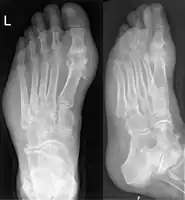

Gout may be diagnosed and treated without further investigations in someone with hyperuricemia and the classic acute arthritis of the base of the great toe (known as podagra). Synovial fluid analysis should be done if the diagnosis is in doubt.[18][51] Plain X-rays are usually normal and are not useful for confirming a diagnosis of early gout.[7] They may show signs of chronic gout such as bone erosion.[47]